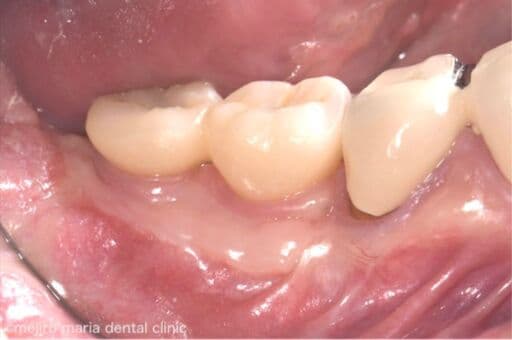

歯肉移植の症例

インプラントを守るために強い歯茎を移植(FGG)

インプラントの周りの硬い歯茎が失われた患者様に対する、歯茎再生の手術(付着歯肉を増やすための歯茎の移植)を行った症例です。

| 治療内容 | 遊離歯肉移植術(FGG) |

|---|---|

| 治療期間 | 3ヶ月(移植した歯茎が落ち着くまで) |

| 治療回数 | 1回(他、抜糸や経過観察を除く) |

| 治療費用 | 137,500円(税込) |